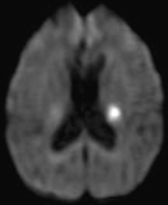

脳梗塞の診断には脳MRI検査が重要で、発症早期から確実に梗塞の部位や大きさを特定することができます。

下図の頭部MRI画像は、突然の右半身脱力で発症した男性で、拡散強調画像という撮像法によって、左大脳深部の小さな脳梗塞が白い異常信号域として描出されています。